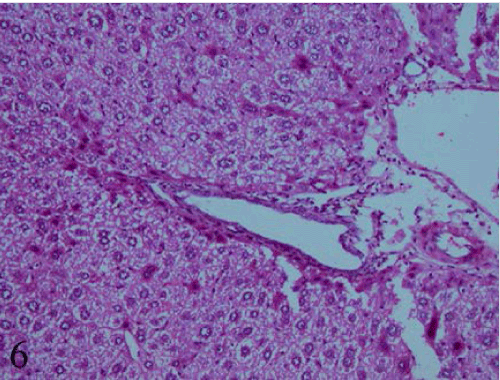

| Figure 6: A section of liver drenched strawberry drink at dose (0.8 mg/kg b.w./day) for 3week showing marked dilatation in portal tract, proliferation in the bile duct epithelial cells.Hepatocytes revealed vacuolar degeneration and peripheral chromatin clumping (Hx &E x200). |